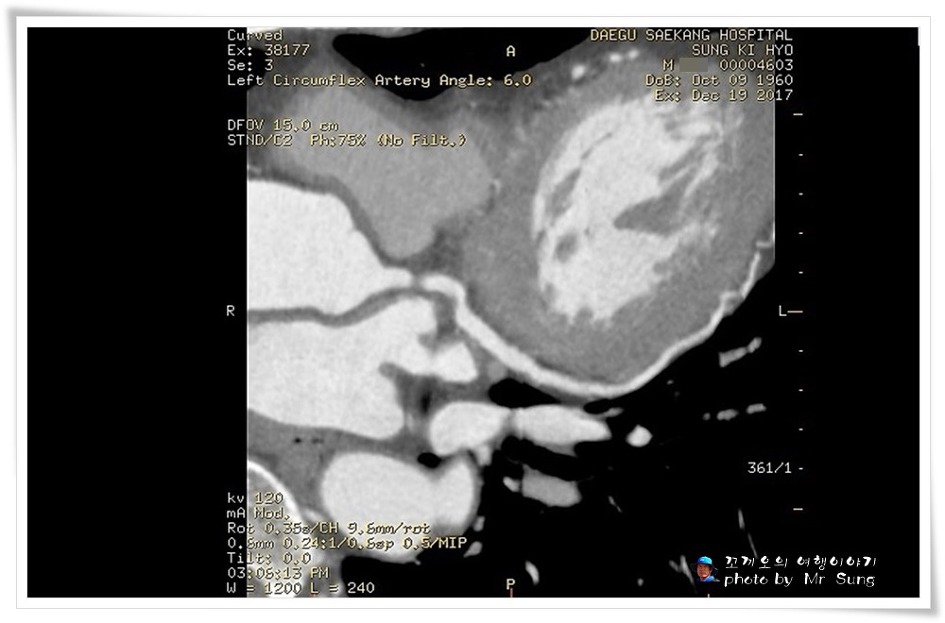

이 사진이 꼬끼오가 실제로 심장(관상동맥) 혈관CT를 촬영한 모습이다.

혈관의 모양이 부풀어오르거나 꽈리의 현상이 없이 정상적으로 혈관이 튼튼하기도 하다.

사람의 몸 속에 깊숙하게 들어있는 혈관은 이렇게 사진을 찍어보지 않고서는 아무도 모른다.

이렇게 무수한 혈관들이 경화가 되면서 혈관이 좁아지거나 막히면 심근경색이나 혐심증이 나타나기도 한다.